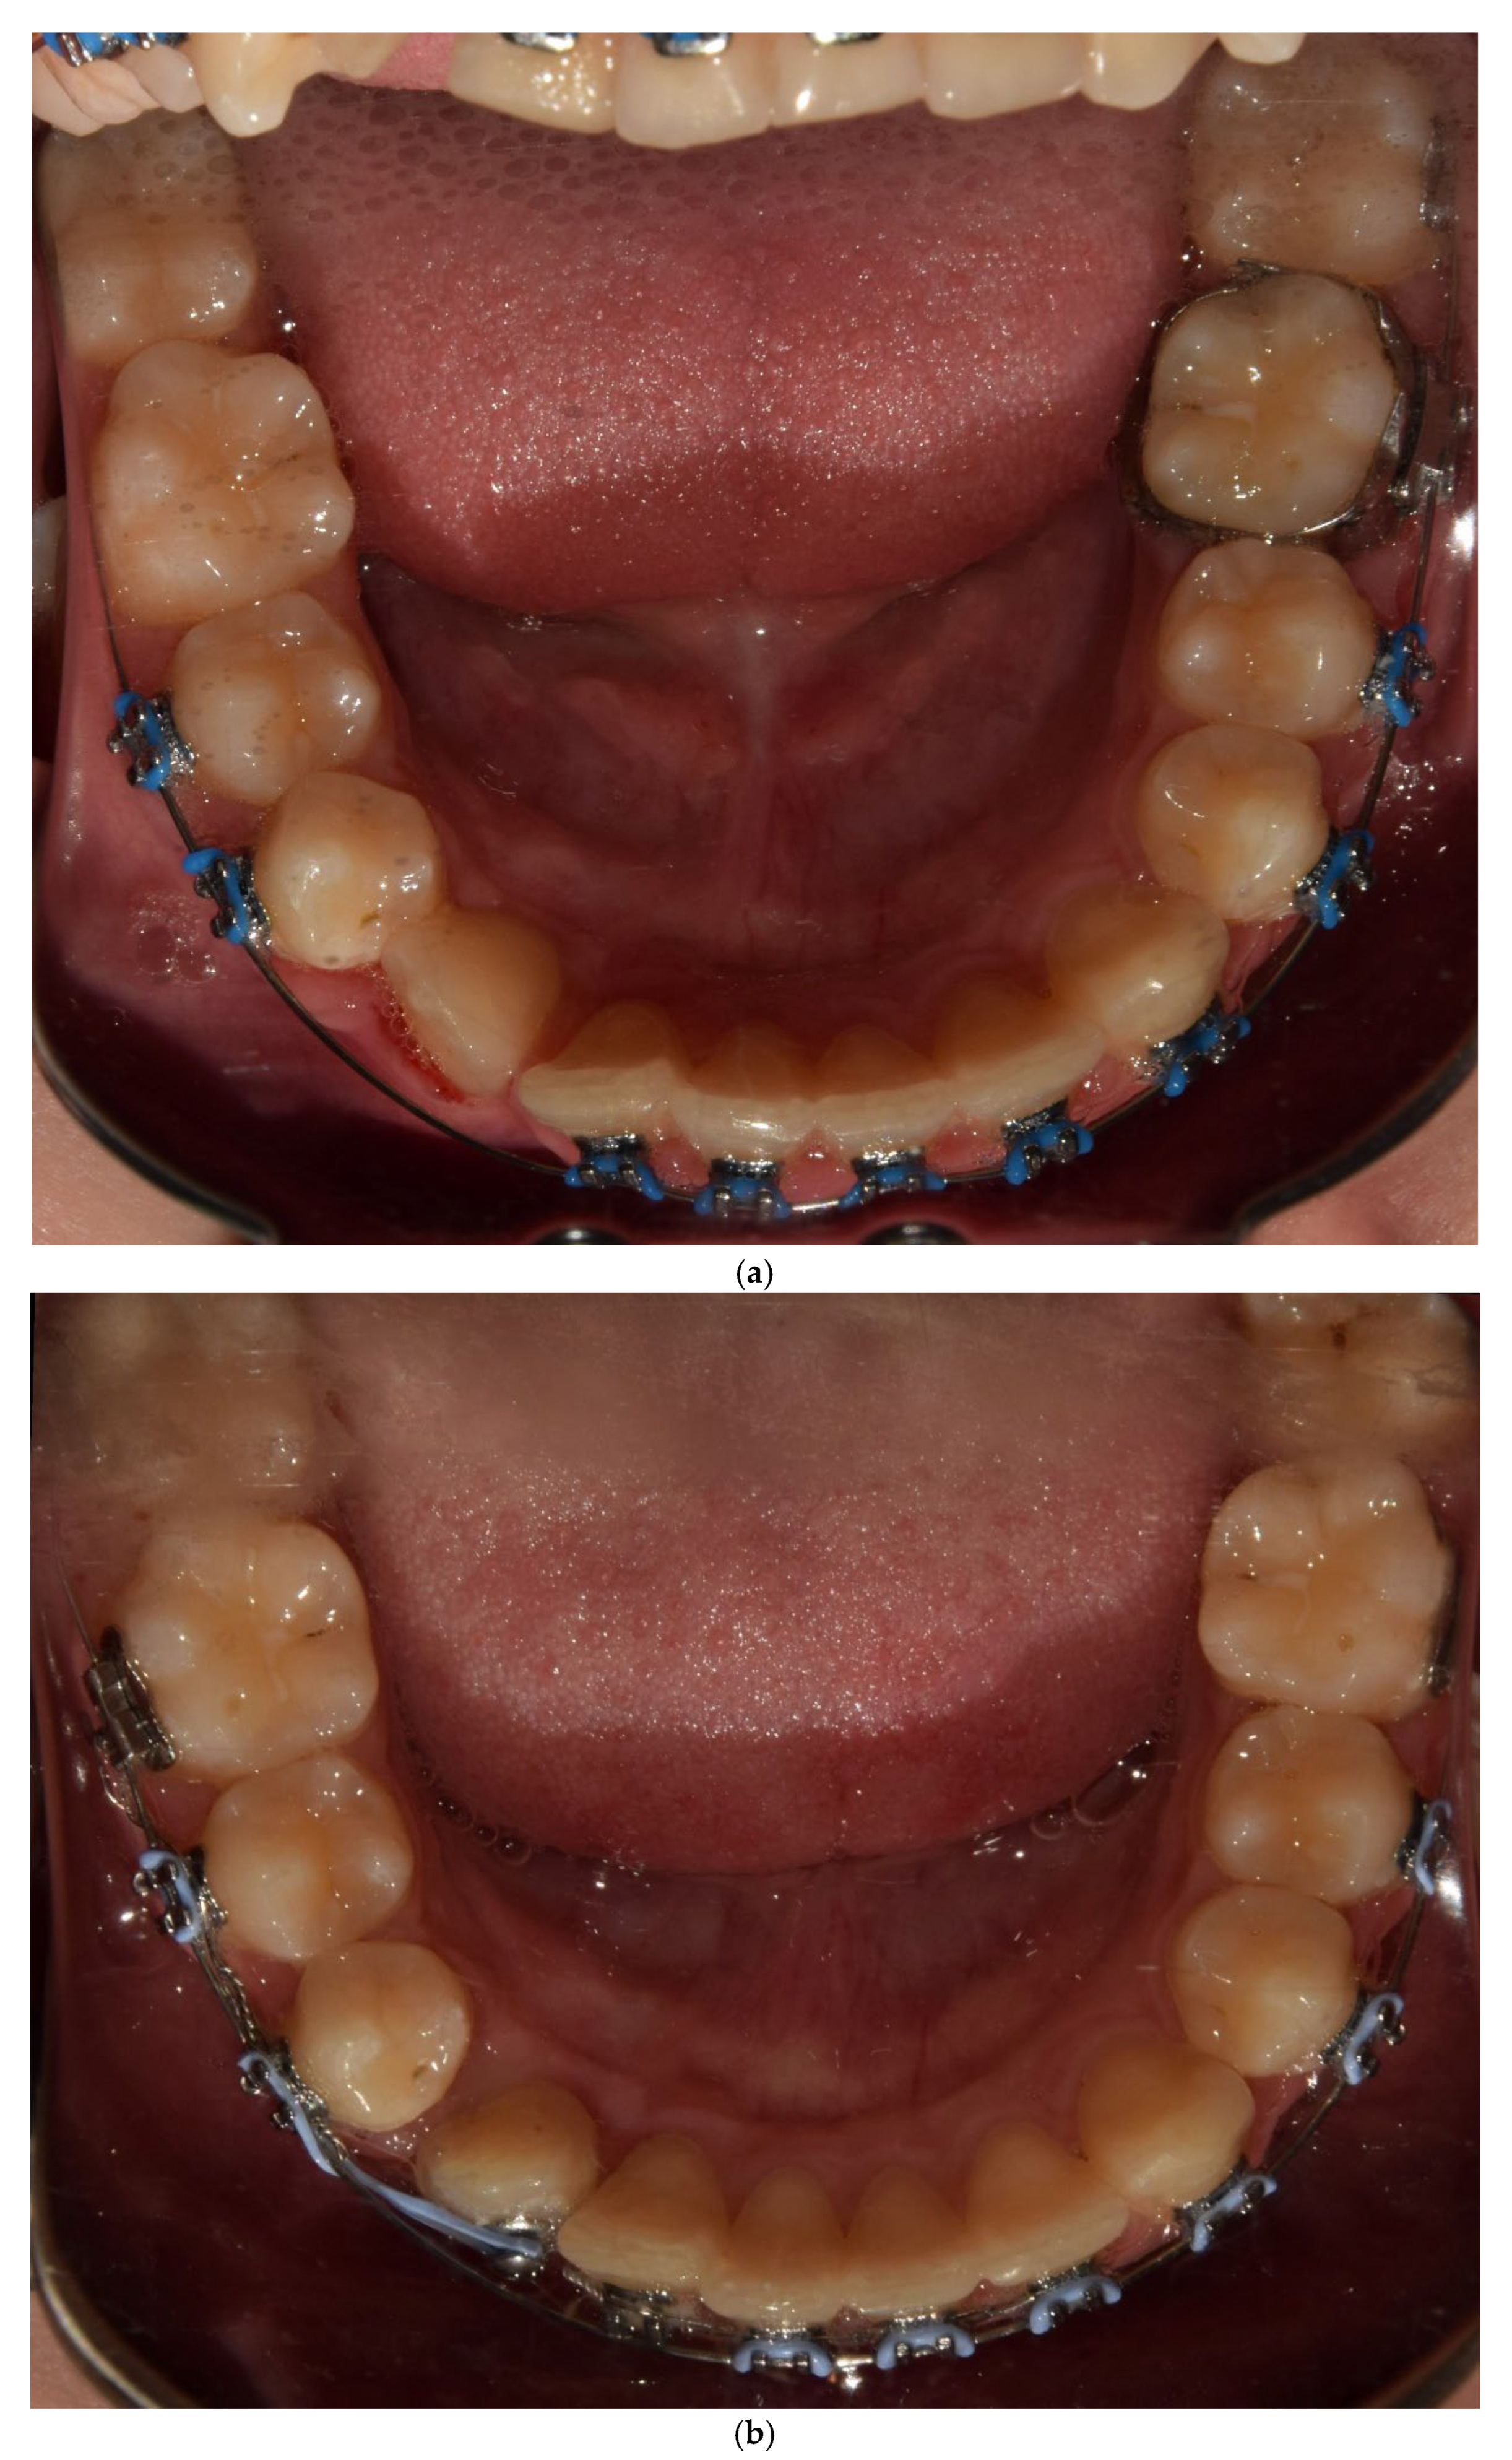

A 13-year-old patient presented with a horizontally impacted lower right canine located beneath the apices of the lower incisors, exhibiting transmigration. The patient had Angle Class I occlusion with no significant dental abnormalities (Figure 1). Following a detailed analysis of the CBCT scan of the mandible (Figure 2), a decision was made to recreate space within the arch and reposition the impacted canine. Given the close proximity of the canine to the roots of the lateral incisors, precise orthodontic traction guidance was required.

Figure 1. Photos before treatment: (a) extraoral, (b) intraoral and (c) models.